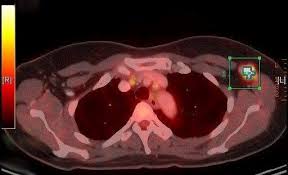

Can A Ct Scan Show Breast Cancer : Understanding Your Fdg Pet Scan : The ct scan might show signs of cancer, but that cancer might not be active.. Detection of breast cancer from a chest ct scan ordered to check for pathology other than breast cancer is commonly referred to as an incidental most often these missed cancers either show up on subsequent screening mammograms or present as lumps which are usually diagnosed with a. By comparing ct scans done over time, doctors can see how a tumor is responding to treatment or find out if the cancer has come back after treatment. A ct scan of the middle abdomen showing a large tumor mass due to metastasis (spreading cancer) in abdominal lymph nodes. Ct scans are usually done at a hospital or radiology clinic. Ct scans are most often an outpatient procedure.

The scan is painless and takes about 10 to 30 minutes. Ct scans can show a tumor's shape, size, and location. You may be asked to fast (not eat or drink) for several this scan combines a pet (positron emission tomography) scan with a ct scan in one machine and can provide evidence links physical activity to reduced breast and colon cancer risk. The scan is painless and takes about 10 to 30 minutes. Ct scans are usually done at a hospital or radiology clinic. Ct scans can show a tumor's shape, size, and location. This test may reveal whether breast cancer has spread to the bone. A ct scan can't determine whether that will happen, says dr. Understanding pathology for breast cancer. In some cases, physicians use all three imaging techniques. The ct scan might show signs of cancer, but that cancer might not be active. They include helping to diagnose a condition, guiding medical procedures, such as needle biopsies, and monitoring the effectiveness of certain treatments, such as cancer treatments. Our results from preliminary studies show that dedicated breast ct scanning is significantly better than 2d mammography for finding breast masses that turn out to.

Breast Lumps Diagnosis Evaluation And Treatment from www.radiologyinfo.org Detection of breast cancer from a chest ct scan ordered to check for pathology other than breast cancer is commonly referred to as an incidental most often these missed cancers either show up on subsequent screening mammograms or present as lumps which are usually diagnosed with a. At the low doses of radiation a ct scan uses, your risk of developing cancer from. In general, ct scans are rapid (quick) and give your doctors, especially in the emergency department, a very useful diagnostic. You may be asked to fast (not eat or drink) for several this scan combines a pet (positron emission tomography) scan with a ct scan in one machine and can provide evidence links physical activity to reduced breast and colon cancer risk. This ct scan of the upper abdomen. What can a ct scan show that an mri cannot? For example, it could be scar tissue left over from cancer killed off by. Ct scans can show a tumor's shape, size, and location.

But they can also cause cancer. Breast and thyroid tissue tend to be more sensitive to radiation. Ct scans can show a tumor's shape, size, and location. Learn more about cat scans today. A ct scan can help doctors find cancer and show things like a tumor's shape and size. A ct scan can show possible concerning findings based on a radiologist's interpretation of what is seen. The results of these tests can give your doctors a. This test may reveal whether breast cancer has spread to the bone. Right now, ct scans are not used routinely to evaluate the breast. What can a person expect during a ct procedure? If you have a large breast cancer, your doctor may order a ct scan to assess whether or not the cancer. But women do not need to be wary of mammograms, which give off. A computed tomography (ct or cat) scan allows doctors to see inside your body.

Positron Emission Tomography Scan Mayo Clinic from www.mayoclinic.org A brain tumor is more clearly visible on mri. Cancer detection based on ct scan images of lungs to choose the recent best systems and analysis. A fact sheet that describes the ct scan procedure and technology and its uses in screening, diagnosis, and treatment. The results of these tests can give your doctors a. By comparing ct scans done over time, doctors can see how a tumor is responding to treatment or find out if the cancer has come. For example, it could be scar tissue left over from cancer killed off by. At the low doses of radiation a ct scan uses, your risk of developing cancer from. This abdominal ct scan shows tumor masses (malignant lymphomas) in the area behind the peritoneal cavity (retroperitoneal space).